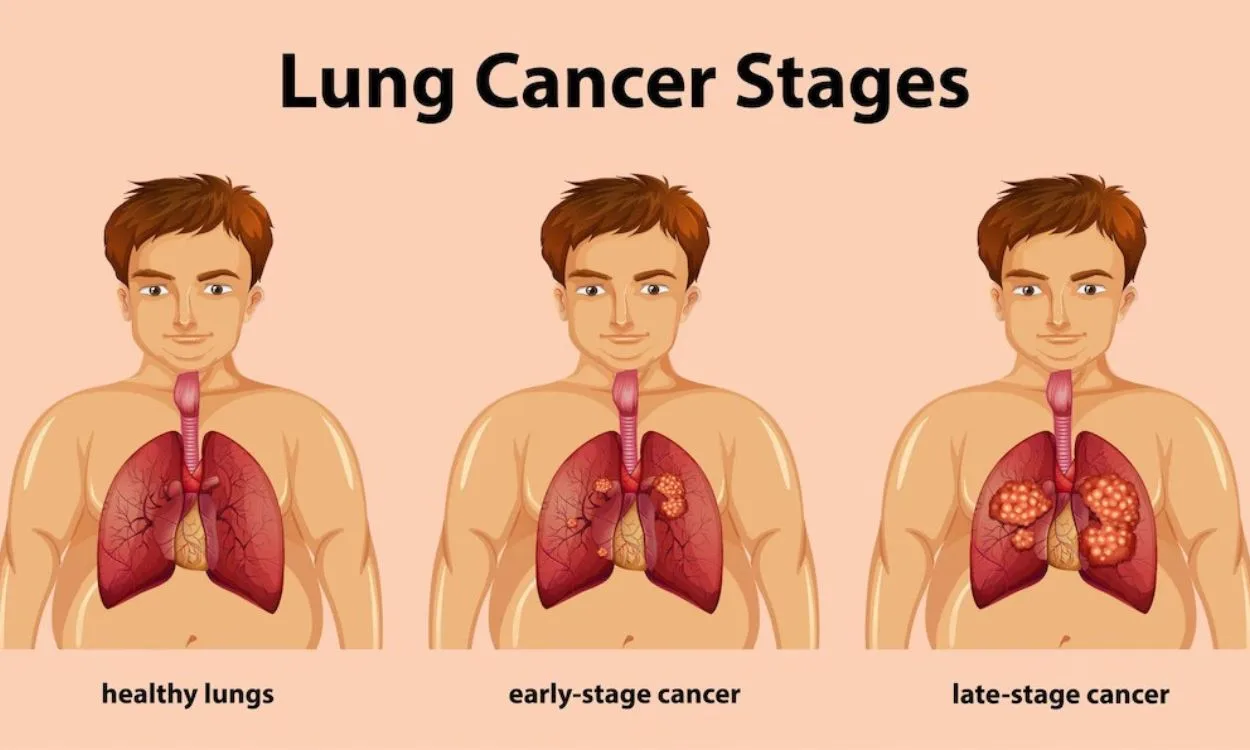

- Lung disease(52)

- Lung Health(52)